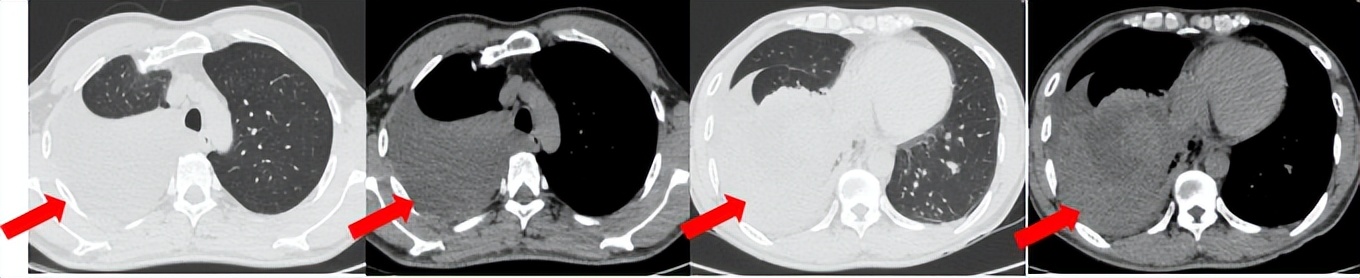

53岁男性,无吸烟饮酒史,脑血栓病史。2024年7月胸部CT:右肺下叶见一团块状软组织密度影,范围约10.8×9.0cm,边界不清,周围并见斑片状磨玻璃密度影,右肺下叶前底段支气管阻塞。纵隔及右肺门见肿大淋巴结影。考虑右肺下叶支气管肺癌。伴纵隔及右肺门淋巴结转移瘤,右下肺静脉瘤栓。2024.7.23行肺穿刺取病理:(肺)腺癌伴有神经内分泌分化。NGS基因检测:RET KIF5B exon15-RET exon12融合。PD-L1(克隆号28-8)TPS=90%。

治疗经过:2024.08开始口服赛普替尼(160mg,bid)。2024.09复查胸CT评效PR。2025.1复查胸CT:右肺下叶外基底段见一不规则形实性肿块,大小约94mm×87mm,边缘呈分叶状,其内密度不匀。右侧胸腔见少许水样密度影。评效PD,PFS=5个月。患者未同意再次组织活检,目前应用卡博替尼治疗,仍在随访中。治疗期间未出现毒性反应。

55岁男性,无吸烟史,有饮酒嗜好。2024年11月常规体检胸CT:左肺上叶占位性病变,大小约2.7×2.4cm,恶性可能大;左肺、左侧叶间胸膜及胸膜下多发微小结节,转移待除外。左侧胸腔积液,部分骨质改变。2024年12月初肺穿刺活检,病理:(肺)腺癌。NGS基因检测:CCDC6-RET(exon1-exon12)融合突变阳性(丰度:13.21%)。PD-L1表达阳性(TPS=35%,CPS=45)。

治疗经过:2025.01开始口服普拉替尼(400mg,qd)。2025.03复查胸CT:左肺上叶、右肺上叶、左肺斜裂见多发实性结节影,长径范围约3-17mm,较大者大小约17mm×12mm,位于左肺上叶下舌段,可见分叶、毛刺、胸膜凹陷、棘状突起征象。纵隔内小淋巴结。评效PR,随访中。治疗期间未出现毒性反应。